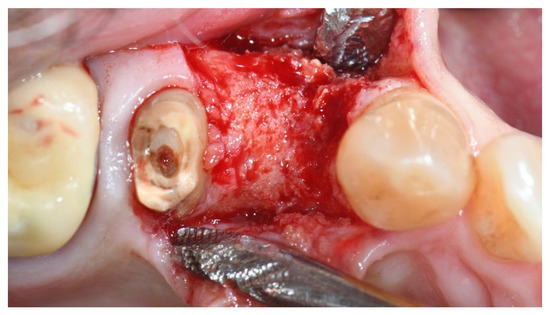

2.2. Clinical Procedures